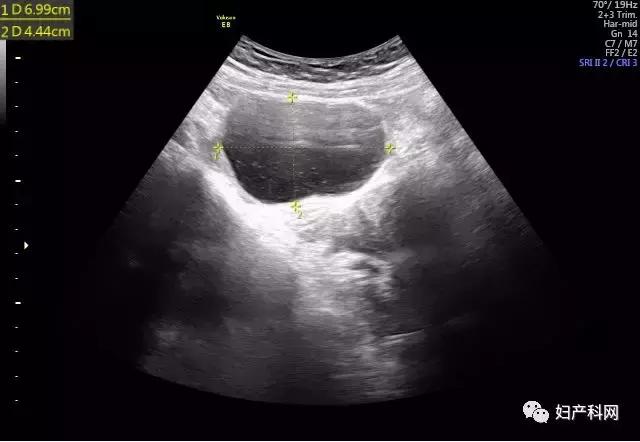

囊肿术前